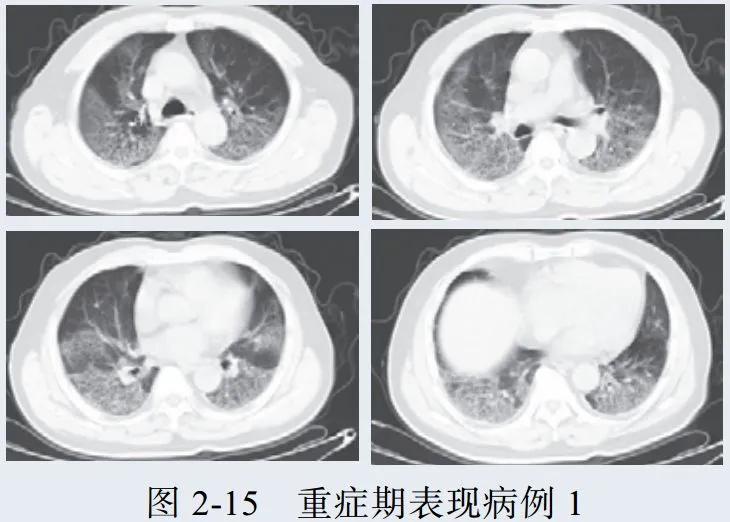

三、重症期征象

新冠肺炎肺部病变一般在发病后 14 天左右达到高峰,少部分病例急剧进展,病变累及双侧全肺,呈白肺征象,其内可见空气支气管征,双侧胸腔可有少量胸腔积液,临床纳入危重症管理

根据既往病理学机制提示肺泡腔有大量纤维素性渗出

病例展示

3. 重症期表现为大范围肺组织密度增高实变,少数呈白肺征象